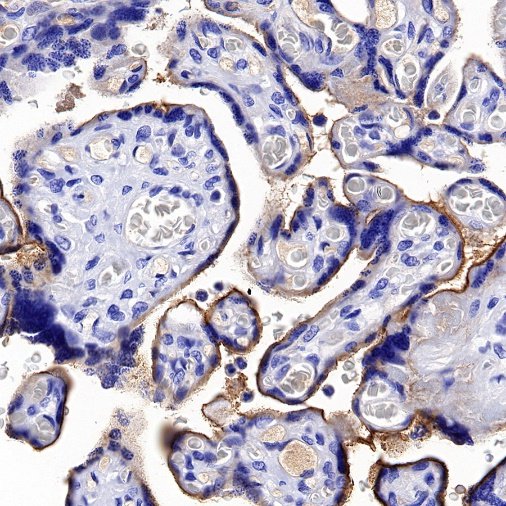

| IHC-P |

1:500 |

null |

Nectin-4 (Nectin cell adhesion molecule 4) is a type I transmembrane cell adhesion molecule belonging to the Nectin family. A homolog formerly known as the poliovirus receptor (PVR/CD155) is also known as the poliovirus receptor associated (PRR) protein. During physiological development, Nectin-4 is specifically expressed during embryonic and fetal development and is very low expressed in adult tissues. It forms physical connections between neighboring cells and is essential for enabling intercellular communication, migration, and other important cellular processes.